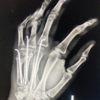

Supracondylar humeral fractures are the most common elbow fractures in children. Historically, the primary treatment for displaced fractures was closed reduction and casting, which often led to Volkmann’s ischemic contracture. In the 1920s, Dunlop introduced traction, reducing severe complications but resulting in lengthy and costly hospital stays. Consequently, surgical intervention became more prevalent. Management of pediatric supracondylar humeral fractures includes non-operative and operative methods, tailored based on factors like fracture type (open or closed), Gartland classification, and physician preference. CRPP is the standard for displaced fractures. However, debate persists about the optimal pinning technique (lateral vs. crossed pinning). In this study of 53 patients, the mean age was 6.62 years, with a peak incidence between 5 and 10 years. This result is comparable to the series done by Patel et al. [12], where they reported a peak incidence in the 6–8-year age group with an average age of 7.48 years. There was a male predominance (56.60% males, 43.40% females) and also noted in Patel et al. [12], Wilkins [13], and Solak and Aydin table no.1 [14]. The left side was more commonly affected (52.83%) compared to the right side (47.16%). According to the Gartland classification, type III fractures were most common. The majority of injuries occurred during playing or recreational activities. For operative treatments, CRPP was the primary method for managing displaced extension type supracondylar fractures. However, there is ongoing debate about the optimal pinning technique, specifically whether lateral pinning or crossed pinning is more effective [15-17]. In a study of 53 patients with SCH fractures, 47 (88.67%) were managed by closed reduction and percutaneous K-wire fixation (CRPP), while 6 (11.32%) underwent open reduction and percutaneous K-wire fixation (ORIF). Overall, 45 (84.9%) were managed with cross pinning and 8 (15.1%) with lateral pinning. Outcomes were assessed using Flynn criteria. For CRPP, 23.4% had excellent outcomes, 57.44% good, 12.76% fair, and 6.38% poor, with 93.61% achieving satisfactory results. For ORIF, 50% had excellent outcomes, 16.66% good, 16.66% fair, and 16.66% poor, with 83.33% achieving satisfactory results. There was no statistically significant difference in age, pain (VAS), or Baumann angle between CRPP and ORIF groups, but significant differences were found in the duration between injury and operation, carrying angle, and m-DASH score. Complications occurred in 24.5% of patients, including one case each of median nerve injury and iatrogenic ulnar nerve injury (both neurapraxias resolved conservatively), vascular compromise in 9.43% of patients, pin site infections in 11.32%, and one case of myositis ossificans. Most neurovascular complications occur with Gartland type III and IV fractures[18], and most surgeons agree that a pink pulseless hand requires immediate closed reduction and stabilization. Louahem et al. [18] examined 26 patients with a pink pulseless hand out of 210 patients with severely displaced supracondylar fractures. In 21 of these cases, pulses returned right after the closed reduction of the fracture. Surgical exploration was recommended for persistent pink pulseless hands only if severe pain or deteriorating neurological function persisted [19]. For cross pinning, 28.88% had excellent outcomes, 53.33% good, 11.11% fair, and 6.66% poor, with 93.33% achieving satisfactory results. For lateral pinning, 12.5% had excellent outcomes, 50% good, 12.5% fair, and 12.5% poor, with 87.5% achieving satisfactory results. There was no statistically significant difference in age, pain (VAS), Baumann angle, or carrying angle between cross pinning and lateral pinning groups, but significant differences in duration between injury and operation and m-DASH score were noted. Cross pinning had a higher risk of iatrogenic ulnar nerve injury. Their major disadvantage of cross pinning is the iatrogenic ulnar nerve injury. The studies estimated it to occur 3–5 times more than lateral pins alone [17,20,21], Hamdi et al. [22]. Overall, fractures generally united in 6–12 weeks without loss of reduction. In our study radiographic outcome, mean 75.9° (range 65°–83°) Baumann’s angle, indicates satisfactory reduction in children’s SCH fractures, with a normal range of approximately 64–81°. The study concluded that CRPP for displaced SCH fractures in children produced favorable results, with a preference for cross pinning despite the higher risk of iatrogenic ulnar nerve injury. Surgical exploration was recommended for persistent pink pulseless hands only if severe pain or deteriorating neurological function persisted [19]. Image 2.

93% patients of our study had satisfactory results according to Flynn criteria, with complete functional ROM and good pain relief along with fracture union around 6–12 weeks with mean carrying angle 7.1° and mean Baumann angle 75.9°. CRPP and ORIF groups had no significant difference with respect to functional outcome. Neurovascular complications most frequently occur with Gartland type 3 and type 4 extension supracondylar fractures.